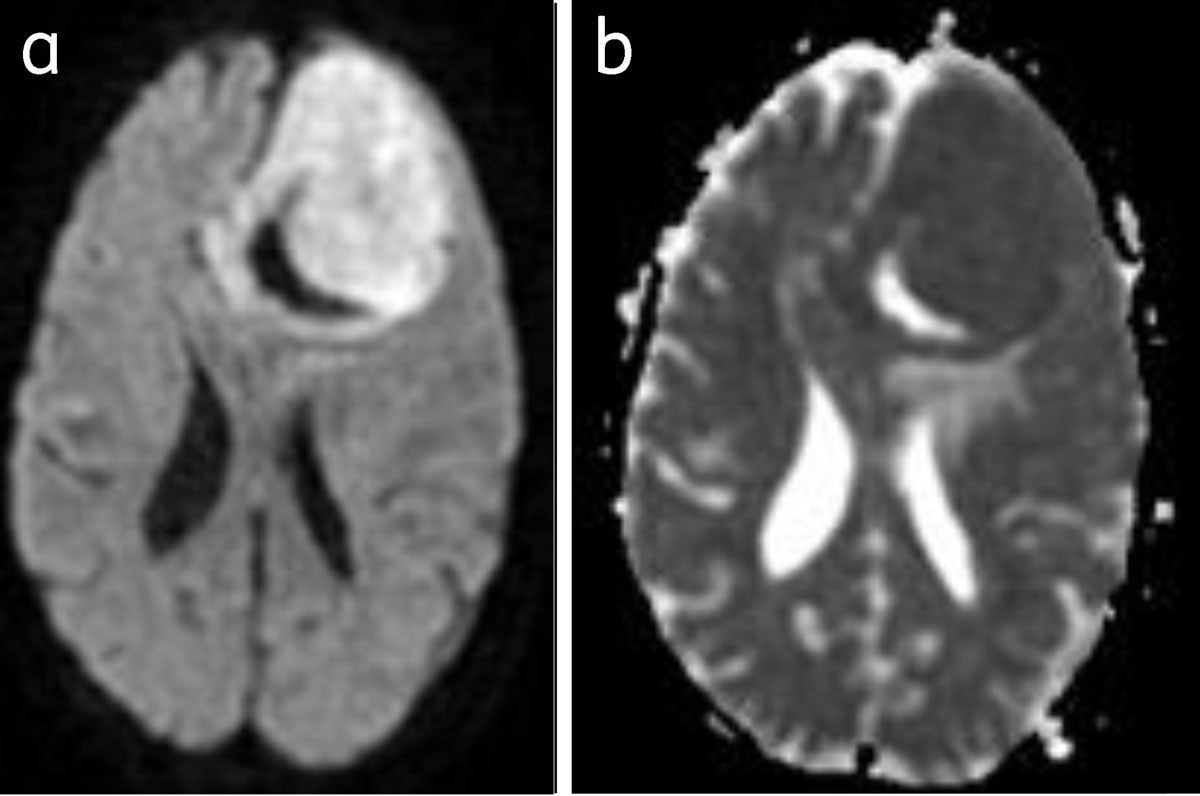

Figure 12

Meningioma with restriction of diffusion: Bright on DWI (a) and dark on ADC (b).